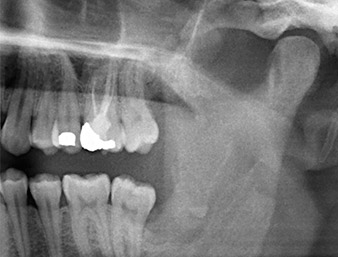

A 26-year old patient complained of constant pain and paraesthesia after surgical removal of a retained wisdom tooth. Panoramic radiographs confirmed a root remnant located in close proximity to the inferior alveolar nerve.

The root remnant in the region of tooth 38 (LL8) was already displaying close proximity to the inferior alveolar nerve on the OPG. The root had fractured during the osteotomy but had not been removed by the primary treatment provider due to intraoperative pain. To ensure as little trauma as possible to the tissue, the new osteotomy was to be carried out using a piezo surgical system. The patient had an unremarkable medical history and was a non-smoker.

It could be seen in the 3D image (digital volume tomography) that the root remnant was located disto-caudally in the transition from the horizontal to the ascending portion of the mandible (Fig. 2).

Based on his medical history, our patient (non-smoker, 26 years old) had a very good chance of a successful outcome. Due to indication of the root remnant’s close proximity to the inferior alveolar nerve on the OPG, digital volume tomography was used in addition (6).